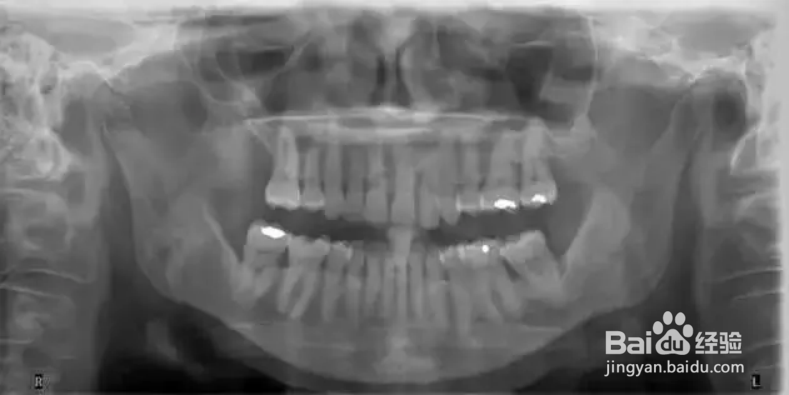

4、全景片,清晰显示关节。另外对牙列有大致概念,但对细节,无法显示得象根尖片或咬翼片那样清晰